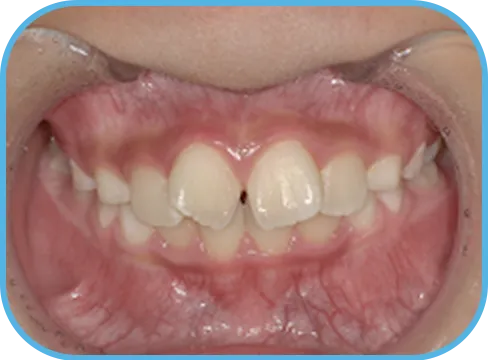

• Before

• 正 面

治療前正面からの歯の様子

• After

治療後正面からの歯の様子

主 訴

上の前歯がねじれている、ガタガタ

治療内容

インビザライン・ファースト

治療期間

8か月

治療費(税別)

450,000円+診断料50,000円

リスク・副作用

• 親知らずの影響や加齢などによって、凸凹が生じる可能性があります。

• 治療の初期段階では痛みや不快感が生じやすくなりますが、1週間前後で慣れます。

• 顎の成長発育によって、噛み合わせや歯並びが変化する可能性があります。

• 状況により当初予定した治療計画を変更する可能性があります。